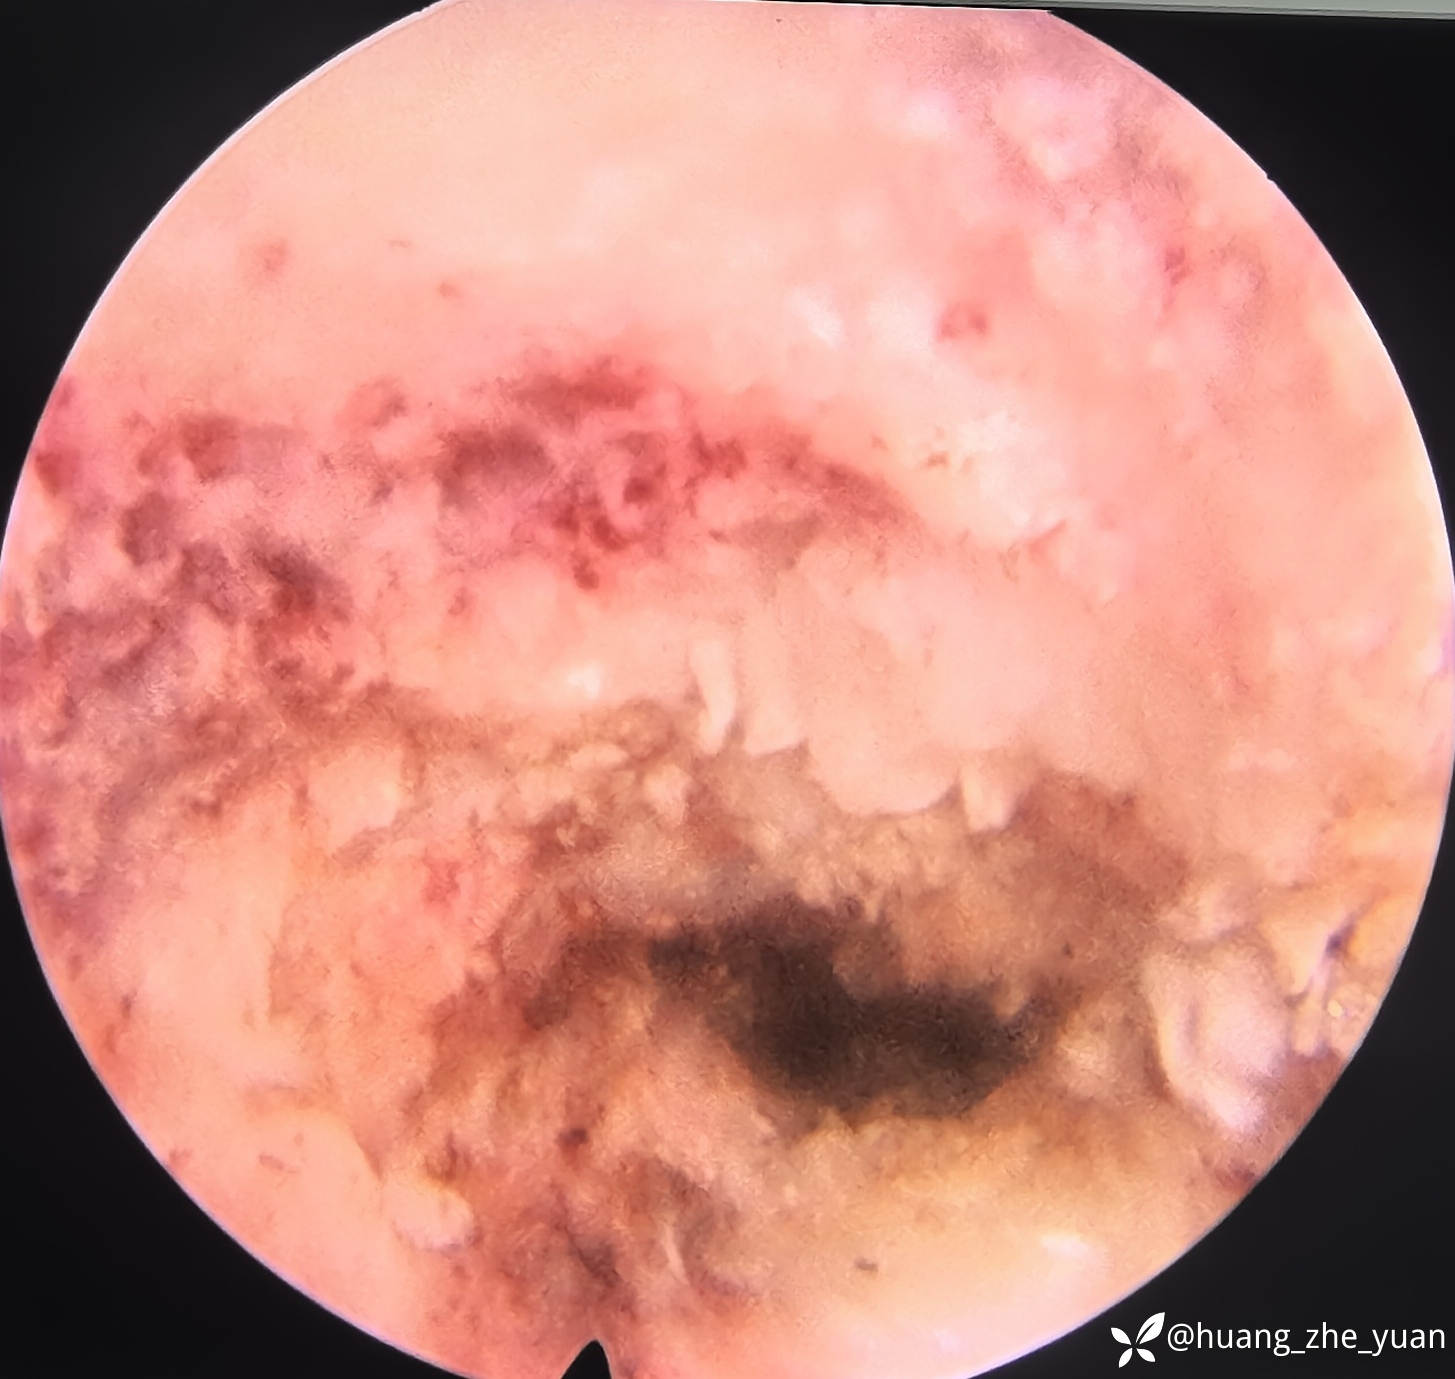

椎间孔少量成形。椎间盘做微创消融。

术后腰痛完全缓解,叩击无痛。术前无法忍受叩击。